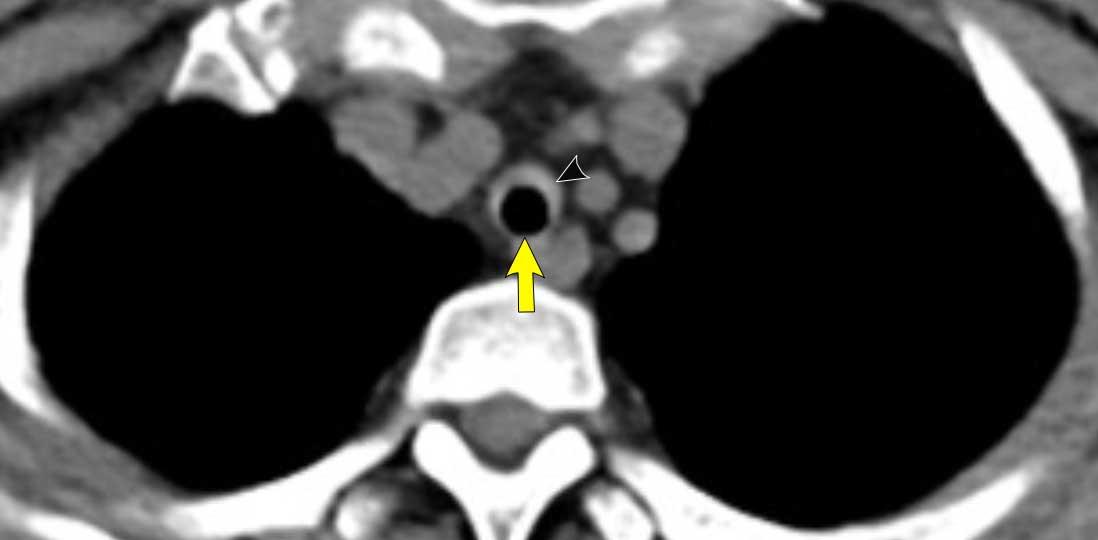

Hình ảnh

Viêm đa sụn tái phát ở bệnh nhân nữ 55 tuổi, cho thấy dày thành đường thở trung tâm do viêm với hình ảnh đặc trưng hình móng ngựa (đầu mũi tên). Không có dày thành sau (mũi tên vàng).